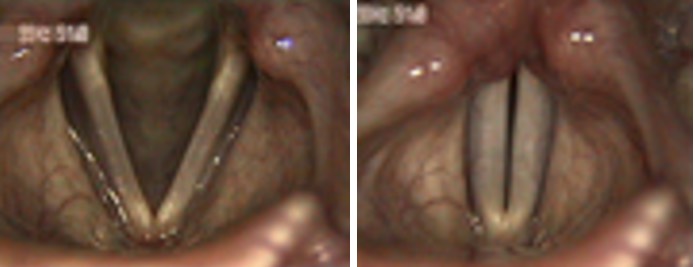

2620. Данная ларингеальная картина характеризует